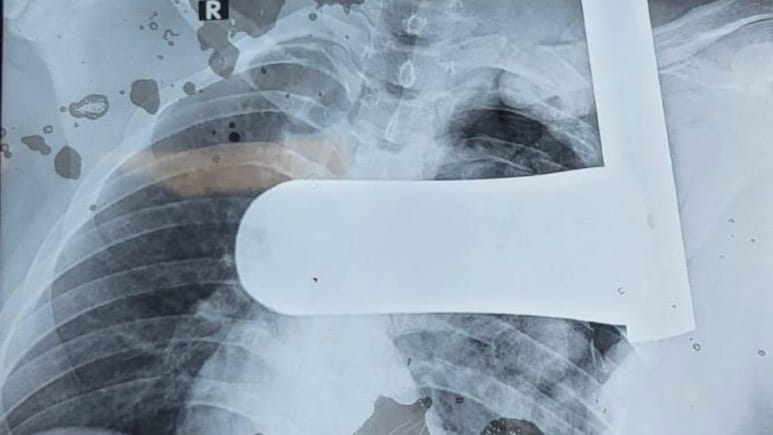

मरीज को बेहद गंभीर स्थिति (शॉक) में उदयपुर लाया गया। रेडियोलॉजी विभाग के  प्रोफेसर डॉ. कुशल गहलोत ने जब सीटी स्कैन किया, तो रिपोर्ट देखकर डॉक्टर भी दंग रह गए. 4 सेमी मोटा लोहे का पाइप पसलियों को तोड़ते हुए फेफड़े को चीरकर गर्दन तक जा पहुंचा था. इससे शरीर की महत्वपूर्ण रक्त वाहिकाएं (सबक्लेवियन धमनी और शिरा) बुरी तरह क्षतिग्रस्त हो गई थीं, जिससे फेफड़ों में आंतरिक रक्तस्राव हो रहा था.

कार्डियोथोरेसिक सर्जन डॉ. विनय नैथानी के नेतृत्व में मेडिकल टीम ने बिना समय गंवाए ऑपरेशन शुरू किया. पाइप 'एल' आकार में फंसा था, जिसे निकालना जानलेवा हो सकता था. डॉक्टरों ने बेहद सावधानी से पाइप निकाला, क्षतिग्रस्त नसों की मरम्मत की, फेफड़ों का उपचार किया और टूटी हुई पसलियों को फिर से जोड़ा.